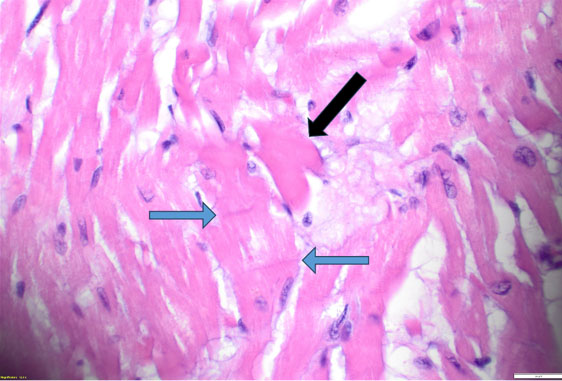

Histopathologic evaluation revealed scattered hypereosinophilic myocytes and contraction bands of the right and left ventricles (Figure 2 and Figure 3), consistent with global hypoperfusion, hypoxia, and catecholamine effect. No organisms were identified. No arteriosclerosis, fatty infiltration, dilated lymphatic vessels, or intercellular proteinaceous deposits existed.

Figure 3: Microscopic image of the left ventricle at 400× shows hypereosinophilic myocytes (black arrow) and contraction bands (blue arrows).